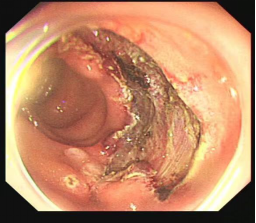

结肠腺瘤的ESD手术

十二指肠溃疡降段早癌的内镜粘膜剥离手术治疗(ESD)

直肠巨大侧向发育型肿瘤,内镜下完整切除(ESD),术后病理证实粘膜内癌,不需追加治疗,达到治愈目的,保留正常器官,避免外科手术。